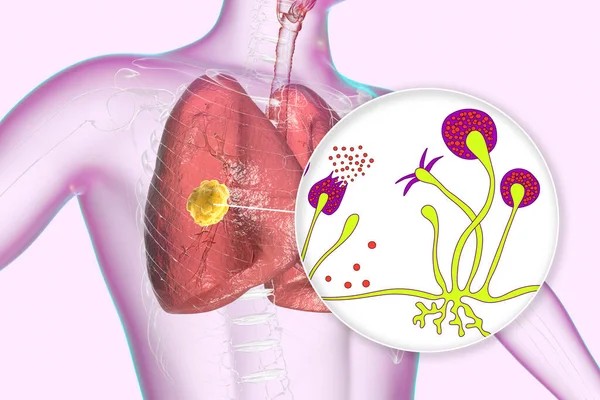

- يصيب النوع الرئوي الرئتين ويظهر غالبا لدى مرضى ضعف المناعة الشديد أو من يخضعون للعلاج الكيميائي.

يعتمد تشخيص مرض الفطر الأسود على مجموعة من الفحوص الطبية الدقيقة التي تهدف إلى تأكيد وجود العدوى وتحديد موقعها ومدى انتشارها داخل الجسم، وتشمل:

- الفحص المجهري للكشف عن الفطريات.

- التصوير المقطعي المحوسب.